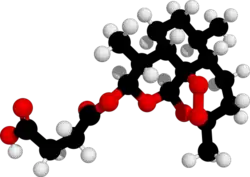

| Formula | C19H28O8 |

| Molar mass | 384.425 g·mol−1 |

| 3D model (JSmol) | |

Chemical synthesis

Artesunate is made from dihydroartemisinin (DHA) by reacting it with succinic acid anhydride in a basic medium. It is one of few semi-synthetic derivatives from artemisinin that is water-soluble.[37][39]